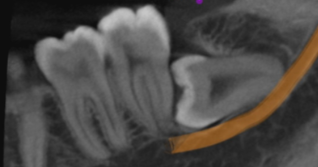

最可靠的方法: 定期进行口腔全景片(曲面断层片)检查,它能一目了然地让所有“躺平”的牙齿无所遁形。

阻生牙,最常见于下颌第三磨牙,即智齿,是指由于邻牙、骨骼或软组织的阻碍,只能部分萌出或完全不能萌出,且本身位置或方向异常的牙齿。

水平阻生 :完全“躺平”,横着顶住前牙。

倾斜阻生 :呈一定角度,斜顶在前牙后背上。